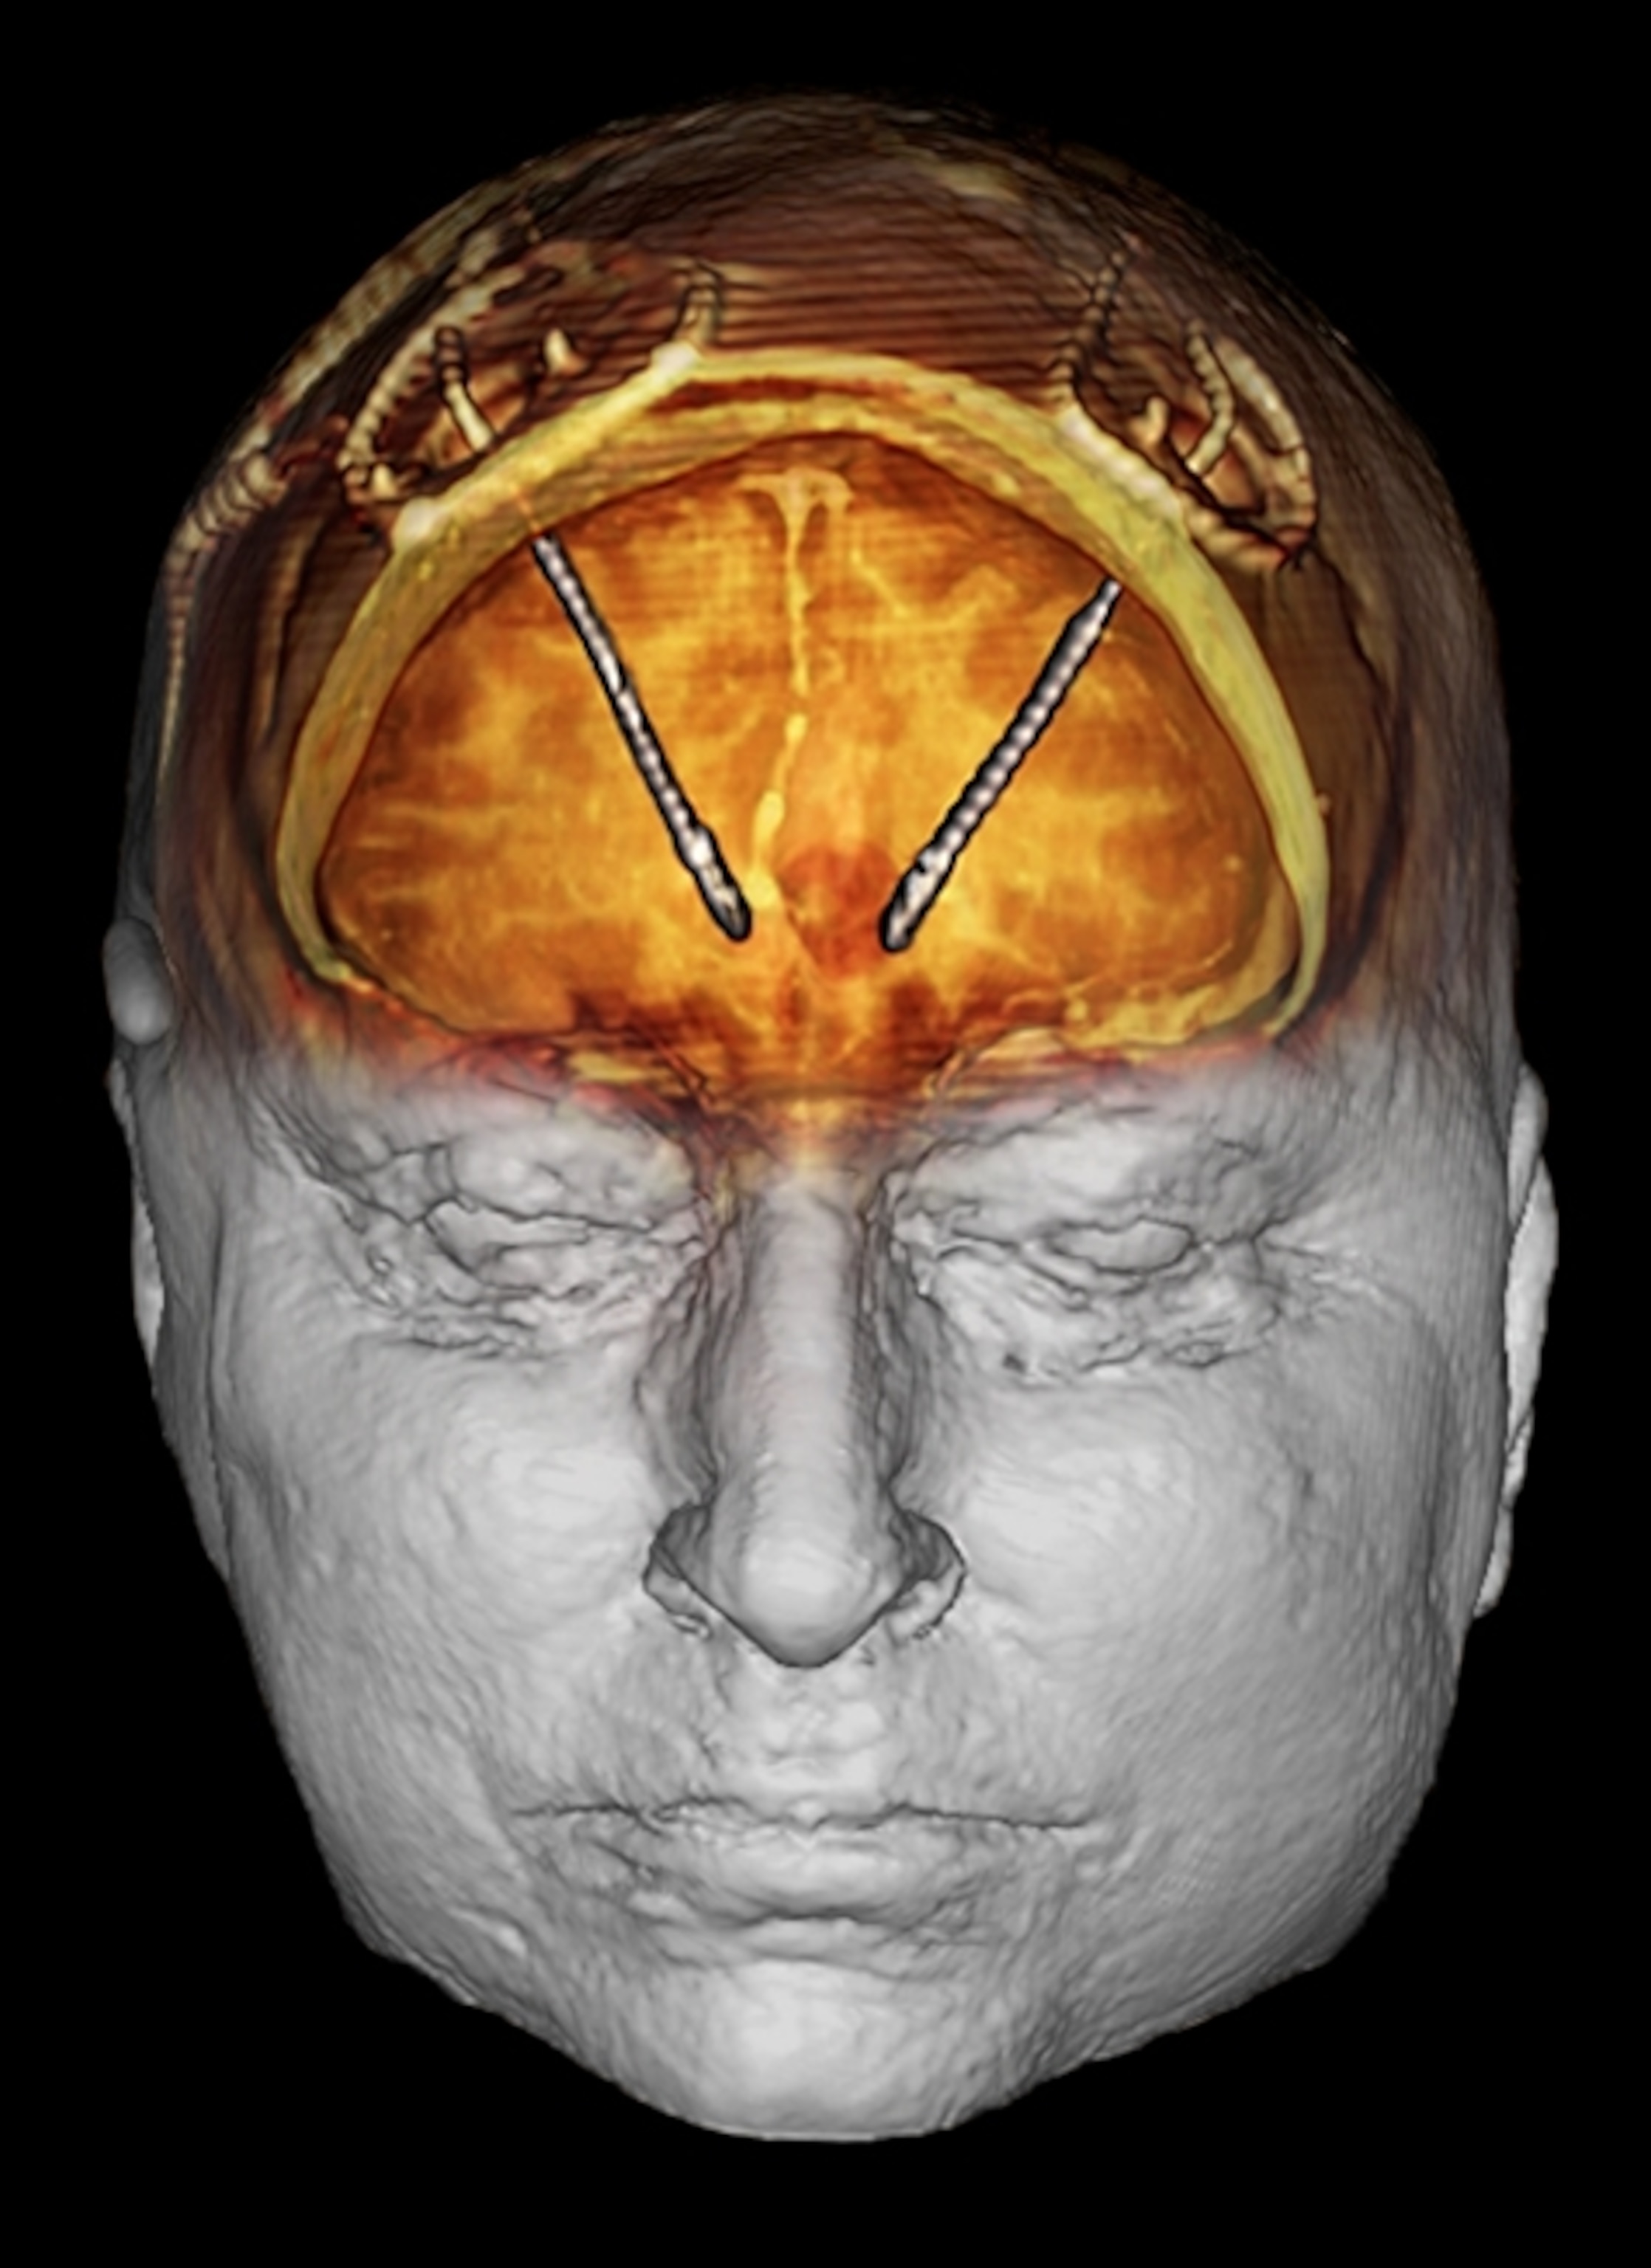

Our perception of pain isn’t limited to merely sensing it. The feelings of unpleasantness, fear, and anxiety that accompany the sensation are an integral part of experiencing pain. In a trial at the Cleveland Clinic, researchers led by neurosurgeon Andre Machado used deep brain stimulation (DBS) to target this emotional component of pain in 10 patients who had chronic neuropathic pain after suffering a stroke. The researchers implanted tiny electrodes in a part of the brain involved in processing emotions. Wired to an electronic device inserted in the chest, the electrodes delivered mild shocks to the implantation site at a rate of nearly 200 a second.